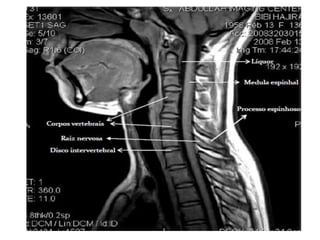

• A coluna vertebral é dividida em cinco

regiões: Cervical, Torácica, Lombar,

Sacro e Coccix.

C3 a C7: Corpo, arco neural posterior,

lâmina, pedículos, processos transversos

e espinhosos.